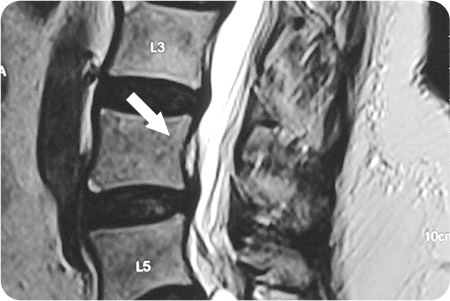

척추내시경 적용사례

1

관절경하

척추디스크 제거술

1cm 내외 절개를 통해 내시경을 삽입해

디스크가 신경을 누르는 부위를 직접 확인합니다.

튀어나온 디스크 조각을 특수 기구로 제거해

신경 압박을 풀어줍니다.